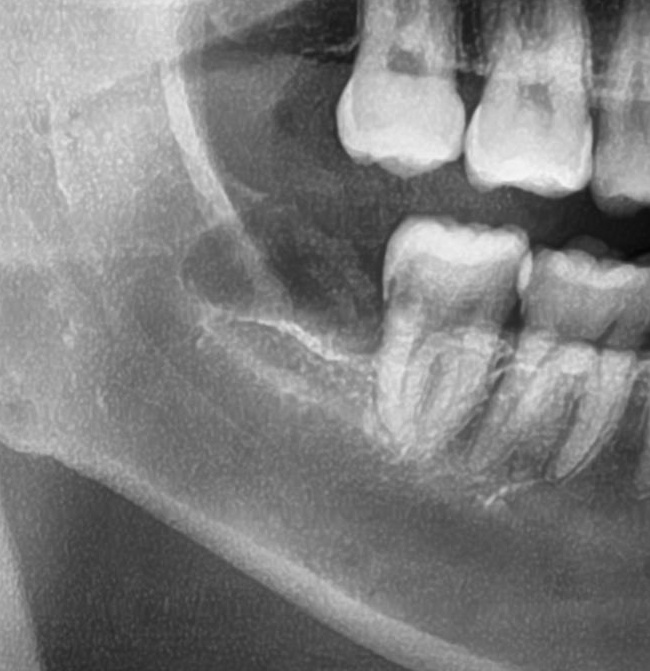

そして4番目の患者様。

年明けに予定していた右上の親知らずの抜歯を行いました。

CTで確認すると、上顎洞に近いため「上顎洞炎」になる可能性がある、難症例です。

事前にお薬を飲んでいだたいていよいよ抜歯開始です。

親知らずは完全に歯茎の中に埋まっている状態のため、まずは歯茎を切開。

親知らずの周りの骨を最小限削っていき、抜いていくスペースを作ります。

そこから親知らずを掴んで慎重に抜いていき、抜歯完了です!